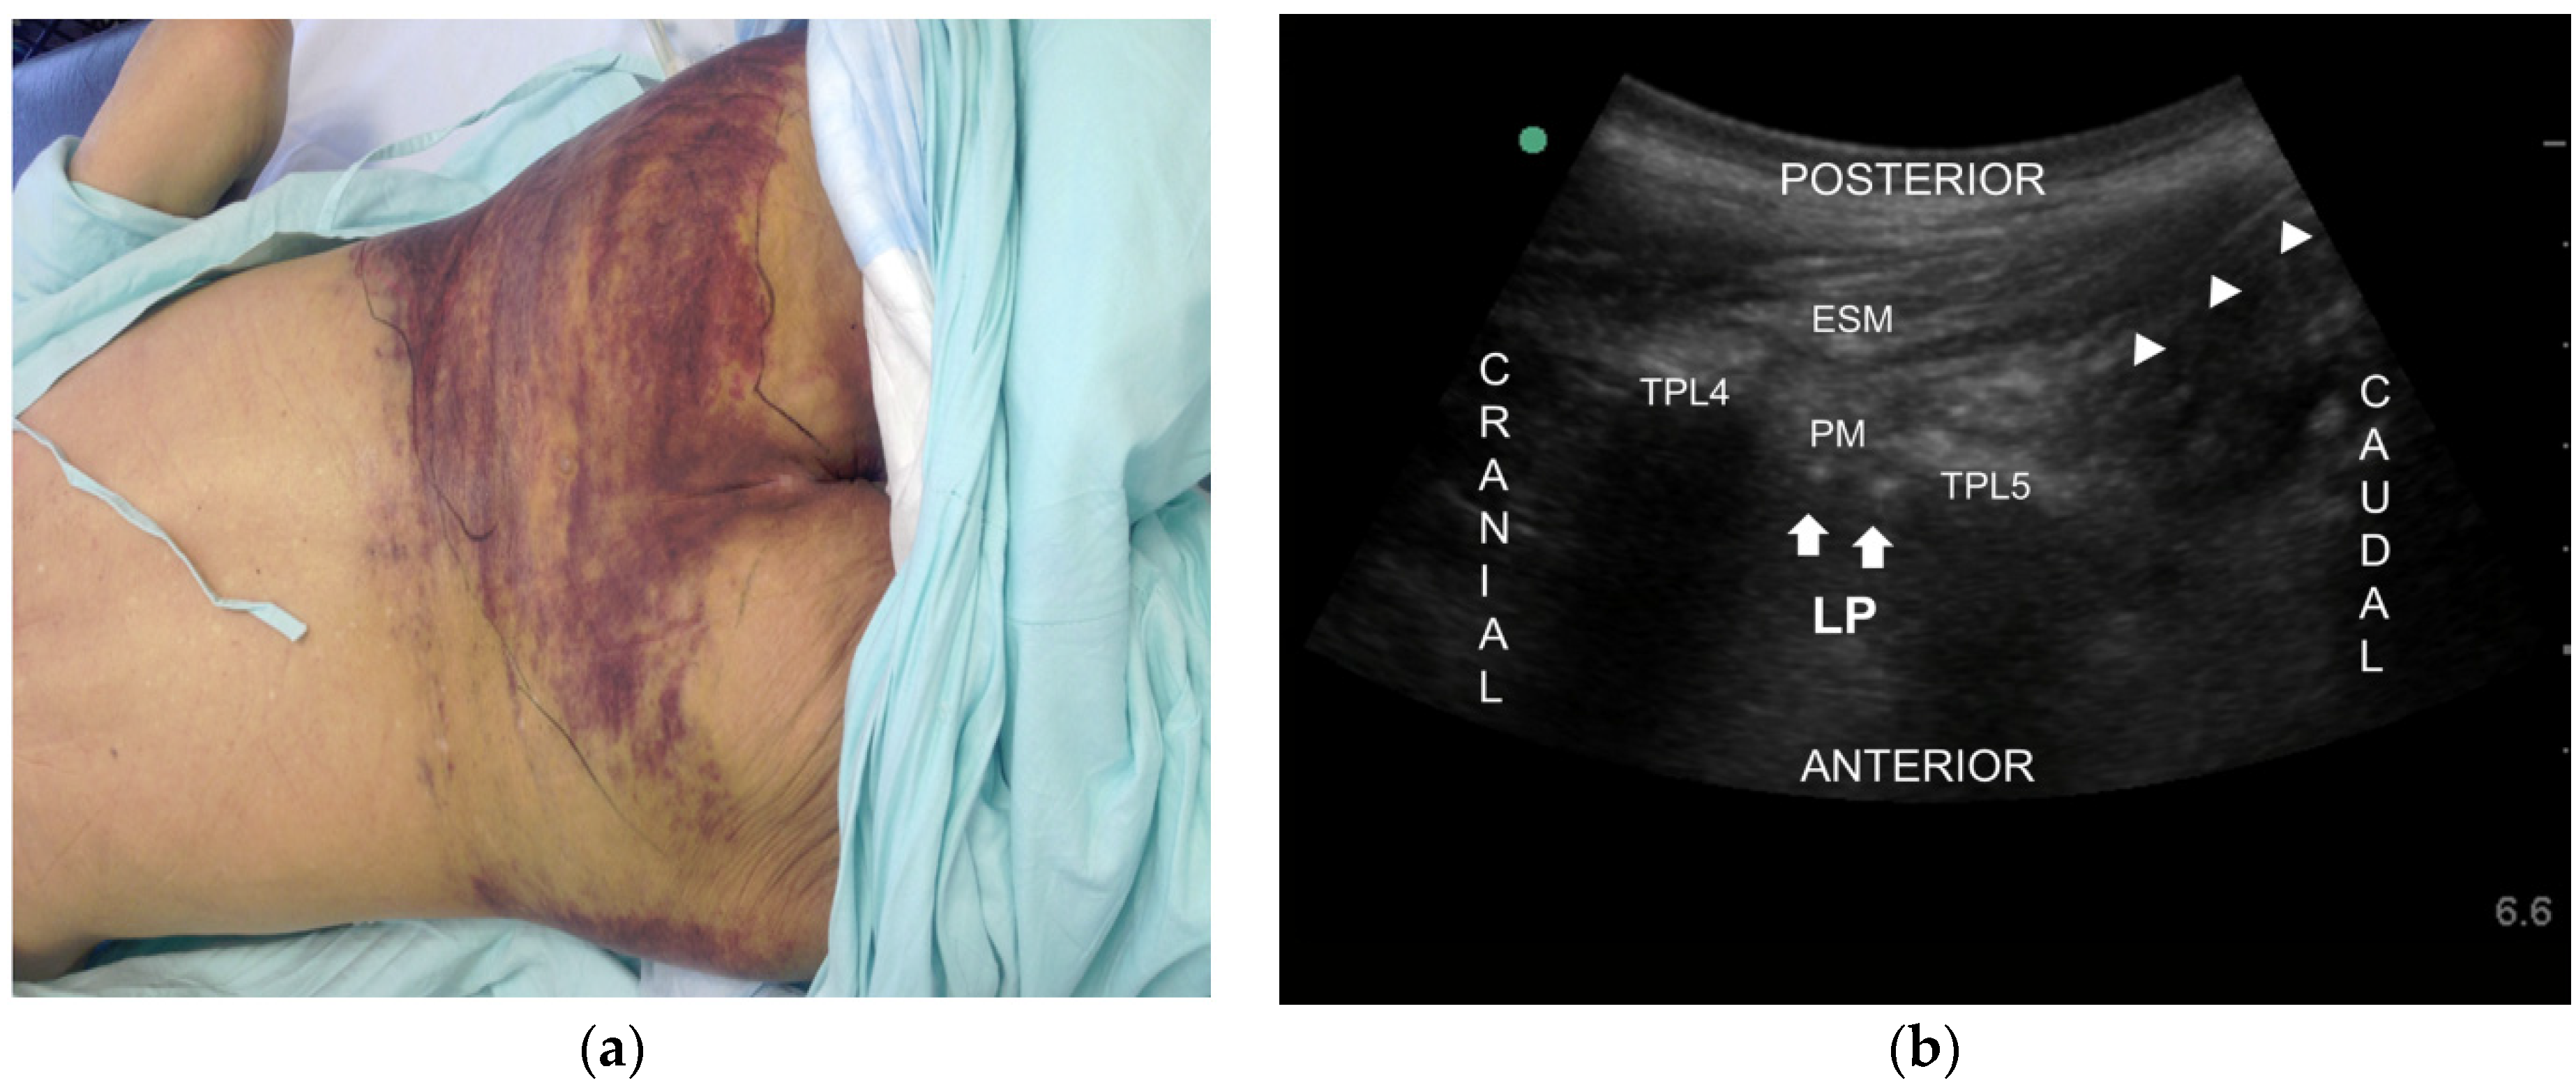

Figure 2.

(a) Picture of severe bruise after fall due to dizziness of adverse effect of medication in Case 2; (b) Ultrasound image of the lumbar plexus block in the posterior part of the psoas muscle (PM). Arrows indicate lumbar plexus (LP). Arrowheads indicate the needle. ESM erector spinae mescle, PM psoas muscle, TPL4 transverse process of L4, TPL5 transverse process of L5.

A 74-year-old man visited our pain clinic for control of a five-year history of left diabetic leg pain. He had suffered from diabetes over 25 years and undergone a right below knee amputation due to a diabetic foot two years earlier. Several comorbidities were present and he had undergone bypass surgery on both legs due to atherosclerosis obliterans eight years earlier. Furthermore, he had suffered a cerebrovascular attack six years prior to his clinic visit, which left sequelae of hemiparesis on his right side. The patient had persistent and severe pain with a burning and tingling sensation from left knee to all toes (VAS 10/10). Pregabalin 225 mg/day, acetaminophen plus tramadol 500 plus 60 mg/day, and nortriptyline 10 mg/day were prescribed. However, his pain was still severe (VAS 9/10). We tried to increase dosage of drug (Pregabalin 300 mg/day) and add opioids (oxycodon 10 mg/day) but in vain. A few days later, he revisited complaining of a fall due to dizziness (Figure 2a). We could not caudal epidural block because of a severe bruise. So, we did an ultrasound-guided lumbar plexus block (LPB) with 10 mL of 0.4% lidocaine. With the patient in the prone position, a low frequency curved transducer was positioned approximately 3–4 cm lateral and parallel to the lumbar spine (over the L4 transverse process). The psoas muscle was seen between the transverse processes and part of the lumbar plexus was also seen as hyperechoeic dots in the posterior part of the psoas muscle. The needle (BD, Singapore, Singapore, 60 mm 24G) was inserted in-plane from the caudal end and advanced into the posterior part of the psoas muscle. After negative aspiration through the needle, the drug was injected in real time (Figure 2b). The VAS decreased from 9/10 to 4/10 for only seven days. After obtaining the patient’s consent form and institutional review board approval (KC13ZISE0739), an ultrasound-guided LPB was performed again with 0.1% bupivacaine 10 mL and 50 Botox units (BOTOX®, Allergan Inc., Irvine, CA, USA). Since 50 Botox units were reconstituted in 2 mL of 0.9% normal saline, total volume injected was 12 mL (Figure 2b). The VAS of 9/10 subsequently decreased to 2/10. At four months follow-up observation, the patient’s pain was well controlled (VAS 2/10).